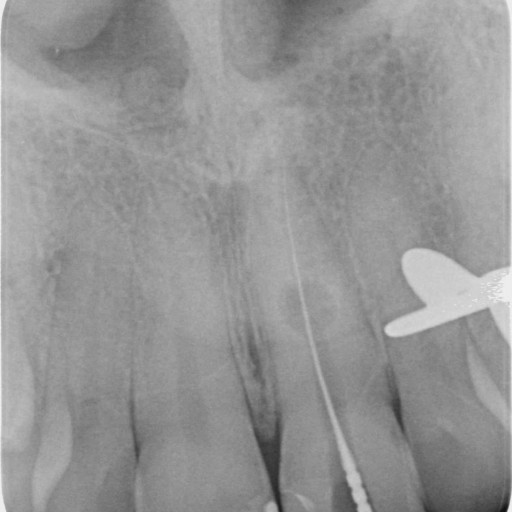

K reeendodontickému ošetření používáme operační mikroskop.

RCRT - Reendodontické ošetření

Nabízíme sekundární ošetření kořenových kanálků. Odstranění ponechaných kořenových nástrojů, odstranění kořenových inlayí.